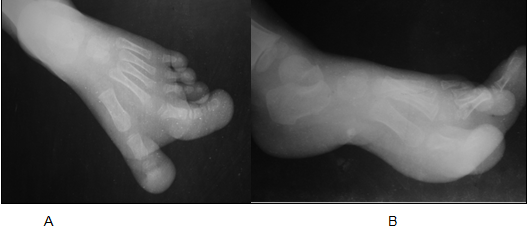

A nine-year-old female presented to radiology department for radiographic evaluation with a long history of progressive disproportionate enlargement of the medial two toes of the left foot. The overgrowth of toes was noticed in childhood which increased progressively with age. Initially it was asymptomatic but later on she developed difficulty in wearing slippers, walking with recurrent injury to the foot. On physical examination, 1st and 2nd toes of left foot were disproportionately enlarged with excessive soft tissue component on the plantar aspect. There was also widening of the web space between 1st and 2nd toes. There were no overlying cutaneous changes, pitting edema or bruit. Rest of the toes of left foot as well as right foot appeared normal. Plain radiography (Figure 2) of the left foot revealed disproportionately enlarged 1st and 2nd toes involving both bony and soft tissue components. There was increase in length and diameter of the involved phalanges with preserved cortex and trabecular pattern. There is also splaying of bony phalangeal ends with dorsal angulation; involving the 2nd toe more markedly. The overgrown soft tissue component showed increased lucency suggesting increased adipose tissue. Biopsy revealed encapsulated lobules of well differentiated fatty tissue extending up to periosteum. Based on typical clinical history, characteristic radiographic findings and histopathology, diagnosis of macrodystrophia lipomatosa was made. |